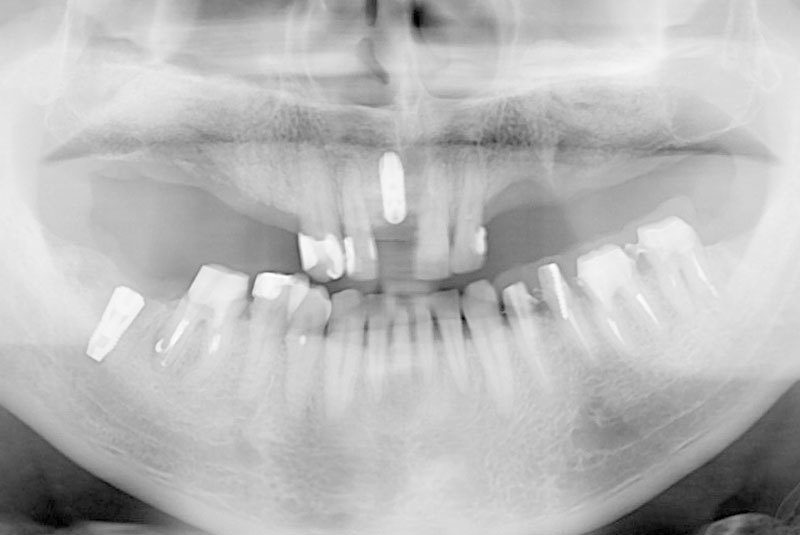

多数歯欠損のインプラント(サイナスリフト・GBR併用)

- 患者

- 50代男性

- 主訴

- インプラントができないかどうか相談。

できるだけきれいにしたい。

- 治療経過

- 前医にて上顎部分入れ歯を装着、下顎の奥歯を抜歯した状態で来院されました。また下顎の両側の臼歯の抜歯が必要と診断されたとのことでした。前医にインプラントを相談したが下顎はできるが、上顎は骨がないことを理由にインプラント不可能と診断され当院受診されました。診断の結果、下顎臼歯は保存可能、上顎臼歯部は左右上顎洞に対する骨造成(サイナスリフト)、前歯部はGBRにて骨造成を行い、インプラント埋入を行いました。

サイナスリフトはかなり専門性の高い外科処置であるため対応できる歯科医師は限られます。そのためショートインプラントや傾斜埋入で対応されることも多いですが、患者さんの年齢や希望を伺いながら当院では必要であれば積極的に行っております。その他不良補綴物の除去、根管治療、虫歯治療を行い全顎に対して審美的修復を行い治療終了までに2年を要しました。ちなみに当院では1本も抜歯は行いませんでした。保存できる歯と抜歯の必要な歯をしっかり診断することも必要です。

- 治療費

- インプラント検査 3万円

臼歯部インプラント(8本) 20万円×8

前歯部インプラント 22万円

サイナスリフト(左右) 20万円×2

GBR(前歯) 5万円

インプラント仮歯 10万円

アバットメント(9本) 7万円×9本

インプラント上部構造(フルジルコニアクラウン) 10万円×10本

インプラント上部構造(ジルコニアレイヤリングクラウン) 12万円

審美修復治療(フルジルコニアクラウン) 10万円×6本

根管治療 健康保険適応

コンポジットレジン修復 健康保険適応

計 509.3万円(税込み)

- 治療回数・期間

- 20回以上 治療期間 約2年